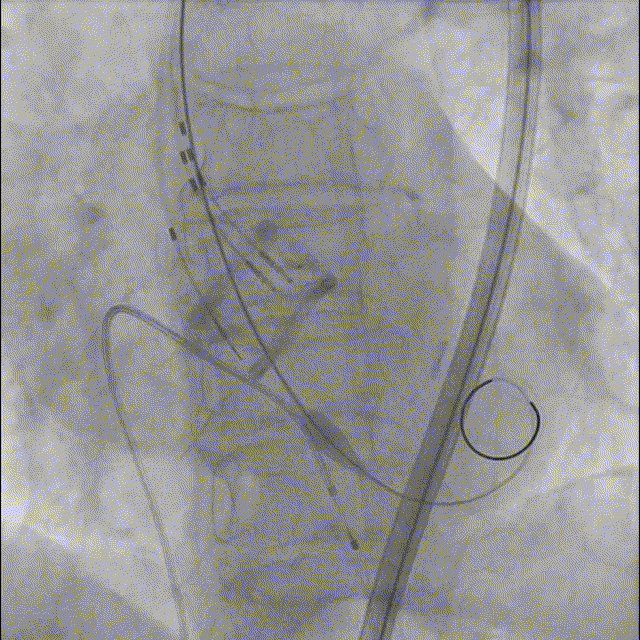

9. Silara A-23mm瓣膜提拉至瓣环水平,精准定位瓣膜,造影剂显示瓣膜功能良好,完成固化;

10. 最终造影瓣膜位置理想,无反流,微量周漏。

最终造影